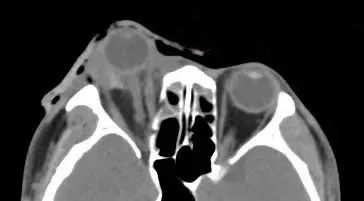

辅助检查的影像学结果显示,陈先生的伤眼近一半已脱出眼眶,眼球壁上还有星星点点的异物存留。

眼球脱出的医学影像示例。(受访者供图)